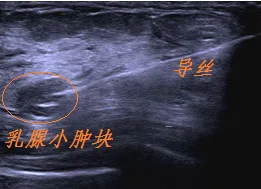

近日,青岛西海岸新区人民医院超声医学科已开展乳腺结节导丝定位技术,在超声引导下利用带倒钩的金属导丝,完成对乳腺小结节的精准定位,帮助外科医生术中快速、准确地找到结节并将其切除,大大缩短了手术时间,为乳腺小结节的术前精确定位提供了有效的方法。

一女性患者超声下发现左乳12点钟位置0.6X0.5cm结节,实性稍低回声,形态欠规则,边界清,血供稍丰富;由于结节较小、位置较深,决定对该患者行超声引导下乳腺结节定位术,术中效果理想,该方法既保证了不漏切病灶,又减少了正常腺体的切除。

目前临床主要依靠影像学引导下导丝定位的方法解决此类问题,通常由超声医学科医生在手术前,用乳腺定位针将导丝置于乳腺病灶中,术中外科医生根据导丝尖端所处的位置来确认病灶,并以导丝为中心做楔形切除。此方法既保证了不漏切病灶,又减少了正常腺体的切除。

常见的乳腺定位针一般为前端带有倒钩的导丝,进针前导丝及倒钩收缩在针鞘内,当针尖进入到病灶中或周边之后,随着针鞘退出,导丝前端的倒钩会自动弹开,固定于病灶内,导丝的尾端固定于乳房的皮肤表面。